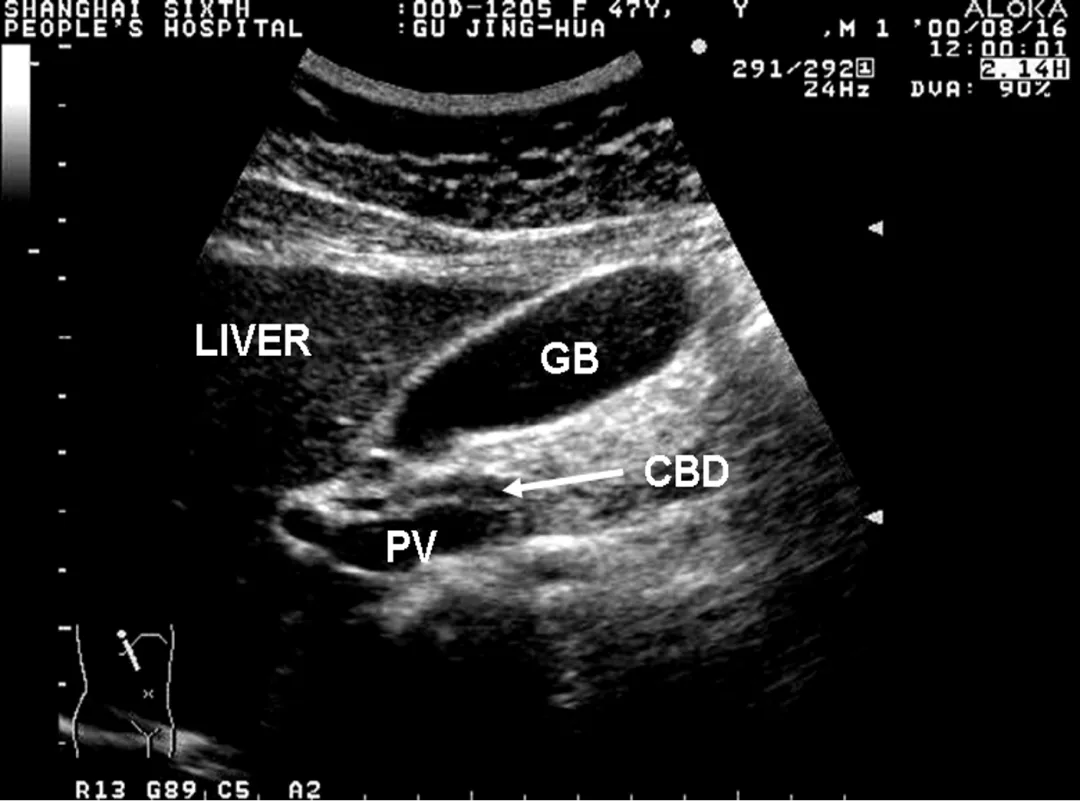

正常超声表现

胆囊位于胆囊窝内

纵切面呈梨形

横切面呈圆形或椭圆形

长径50~80mm, 横径30~40mm,胆囊壁厚度不超过3mm,多数小于2mm。

1:胆囊颈;2:胆囊体;3:胆囊底;4:胆囊皱褶

探头置于右肋缘下,大致与肋弓垂直,左右侧动探头,显示较完整的胆囊长轴断面,测量胆囊的长径和横径。

正常值:长径<10cm,横径<3.5cm